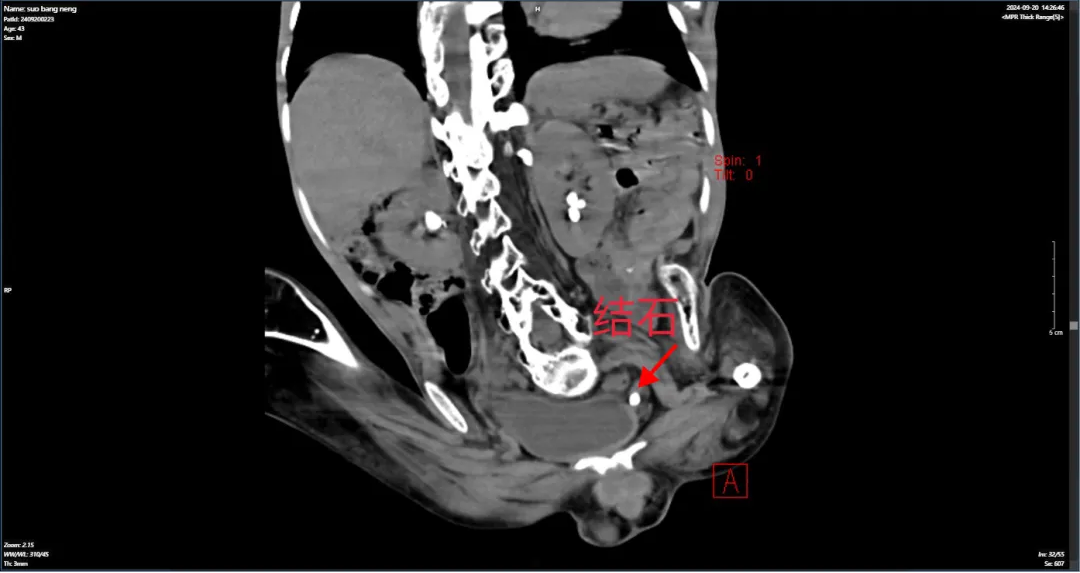

据了解,这位43岁的患者自幼便患有小儿麻痹症,四肢严重萎缩、畸形,长期卧床且日常生活无法自理。最近,突然出现腰痛和尿量减少等症状,被家人送至当地医院检查后,发现其左侧输尿管有结石并伴有左肾积水。鉴于患者身体状况特殊,手术难度较大,加上当地医院医疗条件有限,医生建议转至上级医院进行手术治疗。经多方咨询,得知河池市人民医院泌尿外科在治疗结石及其他泌尿系统疾病方面拥有丰富的临床经验,于是患者在家人的陪同下到河池市人民医院泌尿外科就诊。

入院后,经详细询问病史、查体及结合影像学资料,确诊为“左侧输尿管结石伴有积水和感染”,有手术指征。但因患者脊柱侧弯,腹腔脏器移位,解剖结构改变,且双下肢屈曲畸形,活动受限,大大增加了手术难度。所以术前为了保障患者安全和确保疗效,泌尿外科手术团队立即组织了多学科专家进行会诊,经充分讨论分析,最终为患者量身定制了个体化的治疗方案。